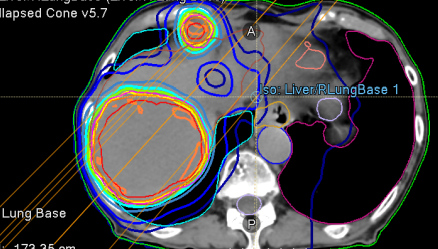

So I see a #lymphoma pt urgently with a large mass in the liver on 10/30/25. We submitted to @AnthemBCBS for authorization for palliative #XRT. They took their time and on 11/12/25, requested a 3D vs IMRT plan. We submitted it, knowing the extra dosimetry work would be done for…